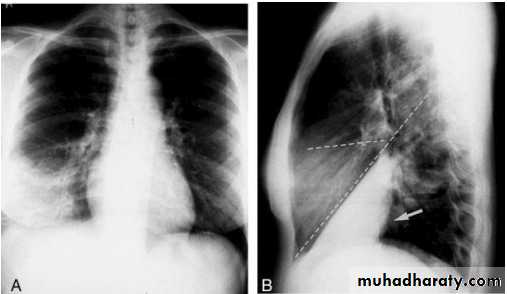

Right lower lobe consolidation - PA. Dense opacification in the right lower zone with effacement of the outline of the right hemidiaphragm.

• Right lower lobe consolidation - Lat.

• The density lies posterior to fthe oblique issure- the position of the lower lobe.